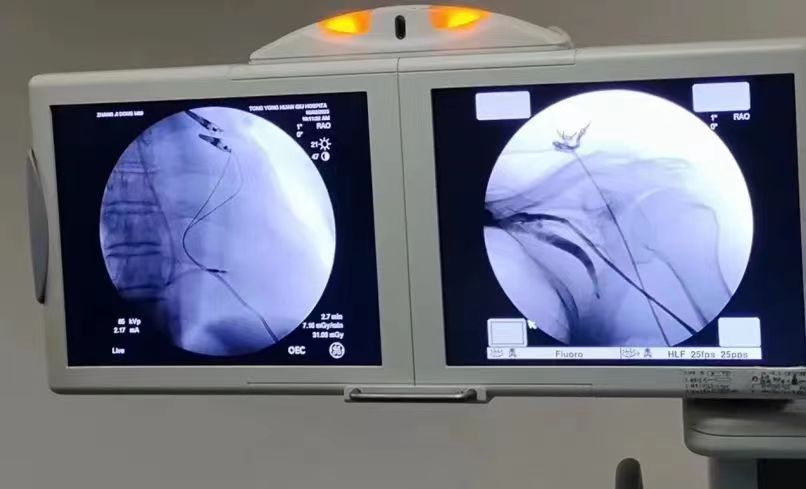

患者為普大型心臟,手術(shù)難度大、風(fēng)險系數(shù)高。手術(shù)過程中,耿蓬勃與陳文璐兩位副主任醫(yī)師一邊精細而嫻熟的操作,一邊對穿刺進針的技巧、電極放置的位置以及患者后期的最大獲益等方面進行了一一講解?;颊叻矫?,他們盡可能的把電極放到一個省電且是窄QRS波的位置,以最大限度延長患者起搏器的使用壽命。整個手術(shù)過程順利。

術(shù)后,患者起搏器各項測試指標均在理想狀態(tài),且無明顯自覺不適,可謂是一場教科書級的手術(shù)演示。